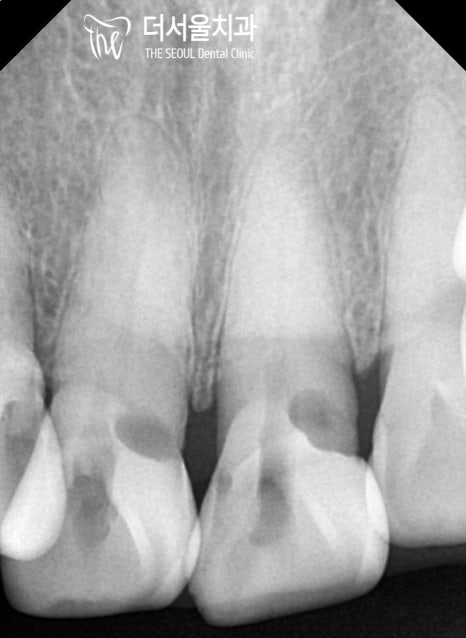

초진 구강 사진을 보면

곳곳에 생긴 우식과 치경부 마모증이

나타나 있는 것을 볼 수 있는데요.

눈에 잘 띄지 않는 곳까지 꼼꼼하게

살펴보는 것이 중요하기 때문에

치근단 방사선을 촬영하여 살펴본 결과

노인에게서 잘 발생하는 치근우식이

나타나 있는 것으로 확인되었습니다.

앞니 주변으로 치근 우식이 생긴 것으로 판단되어

# 11 # 21 엔도 코어 크라운,

# 12 레진 치료